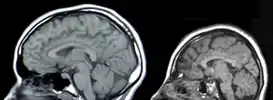

У́мственная отста́лость, ранее — малоу́мие, олигофрени́я (др.-греч. ὀλίγος «малый» + φρήν «ум») — врождённая или приобретённая в период развития задержка либо неполное развитие психики, проявляющаяся нарушением интеллекта, вызванная патологией головного мозга и ведущая к социальной дезадаптации[2]. Проявляется в первую очередь в отношении разума (откуда и название), также в отношении эмоций, воли, речи и моторики.

Умственную отсталость отличают от приобретённого интеллектуального дефекта как следствия деменции (лат. de- «снижение, понижение, движение вниз» + mens «ум, разум»). Приобретённый интеллектуальный дефект — снижение интеллекта от нормального (соответствующего возрасту) уровня после завершения его развития, а при умственной отсталости интеллект взрослого человека в своём развитии так и не достигает нормального уровня. Степень умственной недостаточности оценивается количественно интеллектуальным коэффициентом по стандартизованным психометрическим тестам.[4]